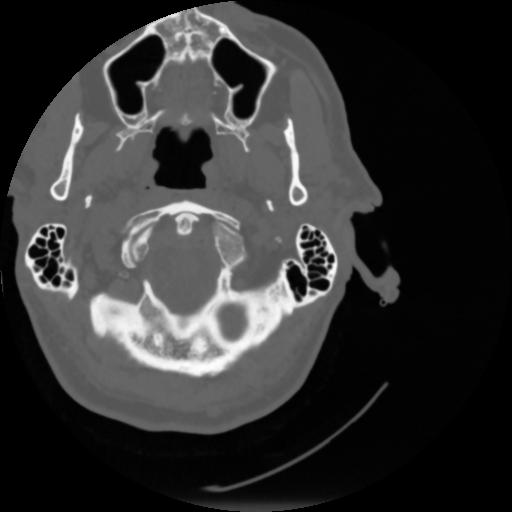

4 CEREBRO,,Vol,0.5,CEREBRO,,